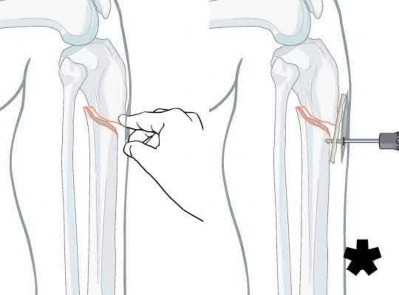

A 31-year-old male sustains an isolated handgun injury shown in Figure A. On physical examination, he has a 0.5 cm wound over the anteromedial aspect of his thigh, with no gross contamination of the skin edges. He is neurovascularly intact. The patient has received tetanus prophylaxis and antibiotics in the emergency department.

This patient has sustained a low-velocity gunshot to the right femoral diaphysis. The next best step in treatment would be insertion of a reamed antegrade or retrograde intramedullary nail. During surgery, the gunshot wound could be closed primarily if it was considered clean, or allowed to heal by secondary intention if it was there was any concern.

Low-velocity gunshot wounds are typically treated as closed fractures, since the risk of osteomyelitis is very low. These are typically bullets from handguns that travel 600 meters per second). The timing and direction (e.g. antegrade or retrograde) of nail insertion has not shown to

affect outcomes.

Cannada et al. reviewed 74 cases of femoral diaphyseal fractures caused by gunshots. All were treated with reamed, retrograde, statically locked intramedullary nailing, without formal irrigation and debridement in the operating room. Outcomes showed low incidence of shortening, angular deformity and infection rate.

Dougherty et al. compared retrograde vs. antegrade intramedullary nailing for the treatment of gunshot diaphyseal femur fractures. No significant differences were found between groups with regards to operative time, blood loss, or radiographic union. They conclude that immediate retrograde or antegrade nailing is safe for the early treatment of gunshot femur fractures.

Figure A shows an AP radiograph of the right femur. There is a gunshot fracture in the proximal femoral shaft with retained bullet fragments. The leg has been placed in temporary traction.